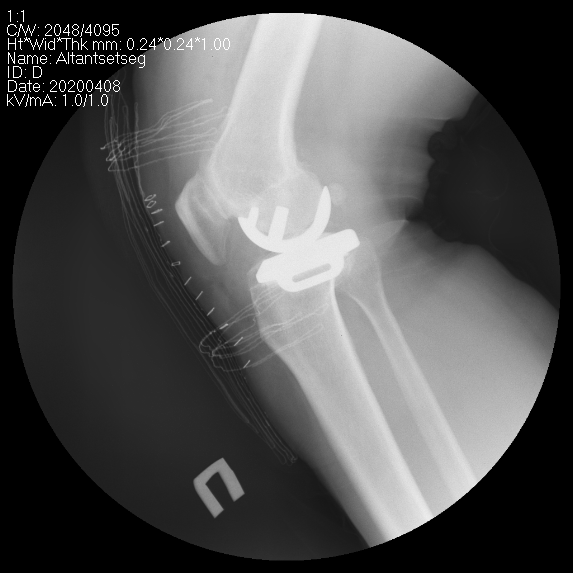

Өвдөгний үе хагас солих мэс засал (UKA) image1

Зураг. Өвдөгний үе бүтэн болон дотор булууг хэсэгчлэн солих мэс засал.